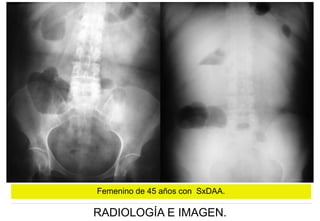

Femenino de 45 años con SxDAA.

Femenino de 45 años con SxDAA con

QUIRÚRGICO:

ENFISEMATOSA

HISTOPATOLÓGICO:

COLECISTITIS AGUDA

GANGRENADA ALITIASICA